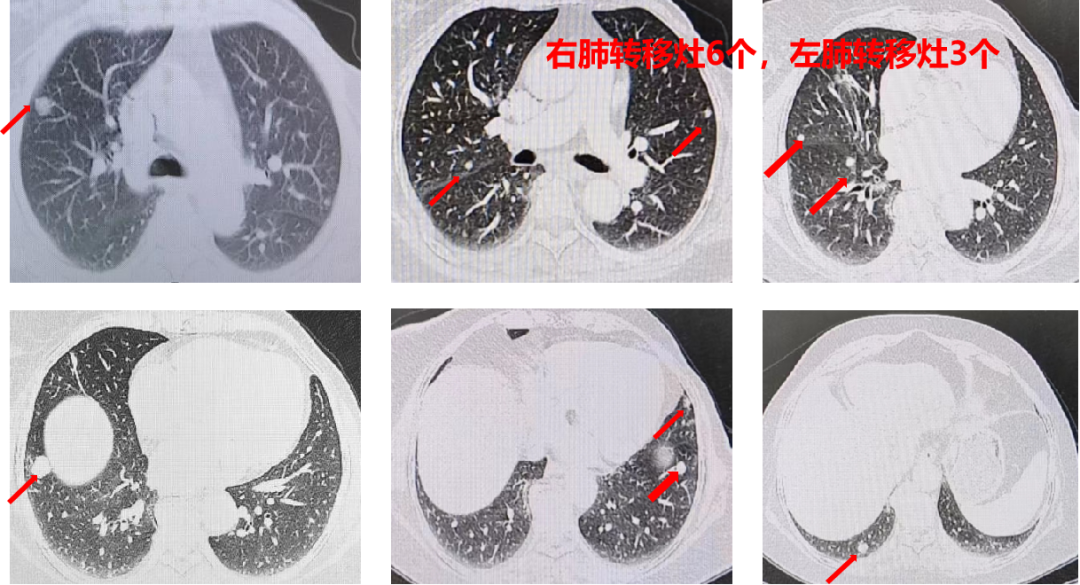

胸部+全腹部增强CT(我院 2021-02-17):直肠壁增厚,考虑直肠癌;盆腔多发稍大淋巴结;肝左叶低密度影,不除外转移瘤;双肺多发结节影,考虑转移瘤(左肺3个,右肺6个,较大者位于右肺下叶,直径约1.6cm)。

盆腔+上腹部增强MRI(我院 2021-02-20):肝左叶异常信号,考虑转移;双肺多发结节影。

直肠壁肿物,肿瘤矢状径:4.2cm;最厚处2.0cm;肿瘤远端距肛缘10.2cm,符合直肠癌表现(影像分期T4aN2Mx);盆腔多发增大淋巴结。

CT引导下肺结节穿刺活检(2021-02-18):坏死组织中可见异型腺体,考虑腺癌。免疫组化结果(2021-02-24):AE1/AE3(+),TTF-1(-),CDX2(+),NapsinA(-),CK20(+)。